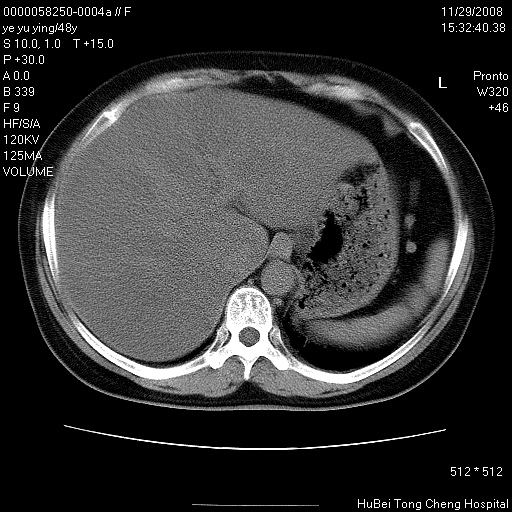

以下是引用zsl6918在2008-11-29 21:47:00的发言:[br]恶性肿瘤病史,转移瘤首先考虑。脂肪肝,胆囊结石。

以下是引用huenhao在2008-11-29 22:11:00的发言:[br]脂肪肝,胆囊结石。左肺病灶建议定期复查。

以下是引用liuyue在2008-11-30 5:44:00的发言:[br]1.左肺病变,首先考虑感染性病变,转移待排;建议治疗后复查。[br]2.肝脏密度普遍减低,考虑与化疗有关。[br]3.胆囊结石.